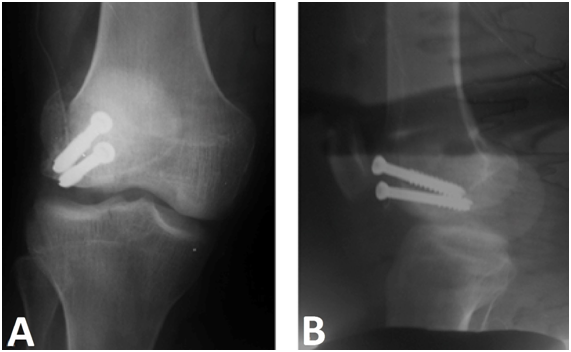

Radiograph of the right knee showed fracture of the posterior aspect of the lateral femoral condyle - Hoffa fracture - type II (Figure 1). CT scan shows fracture of the lateral femoral condyle with a slight misalignment and separation of the fragment, which indicated surgery (Figures 1 & 2). The patient was discharged after surgery, attending since the being accompanied ambulatorially since then (Figure 3).

Figure 3 In A, anteroposterior radiograph and in B, lateral radiograph, demonstrating postoperative synthesis of the lateral femoral condyle fracture with two cannulated screws for large fragments.